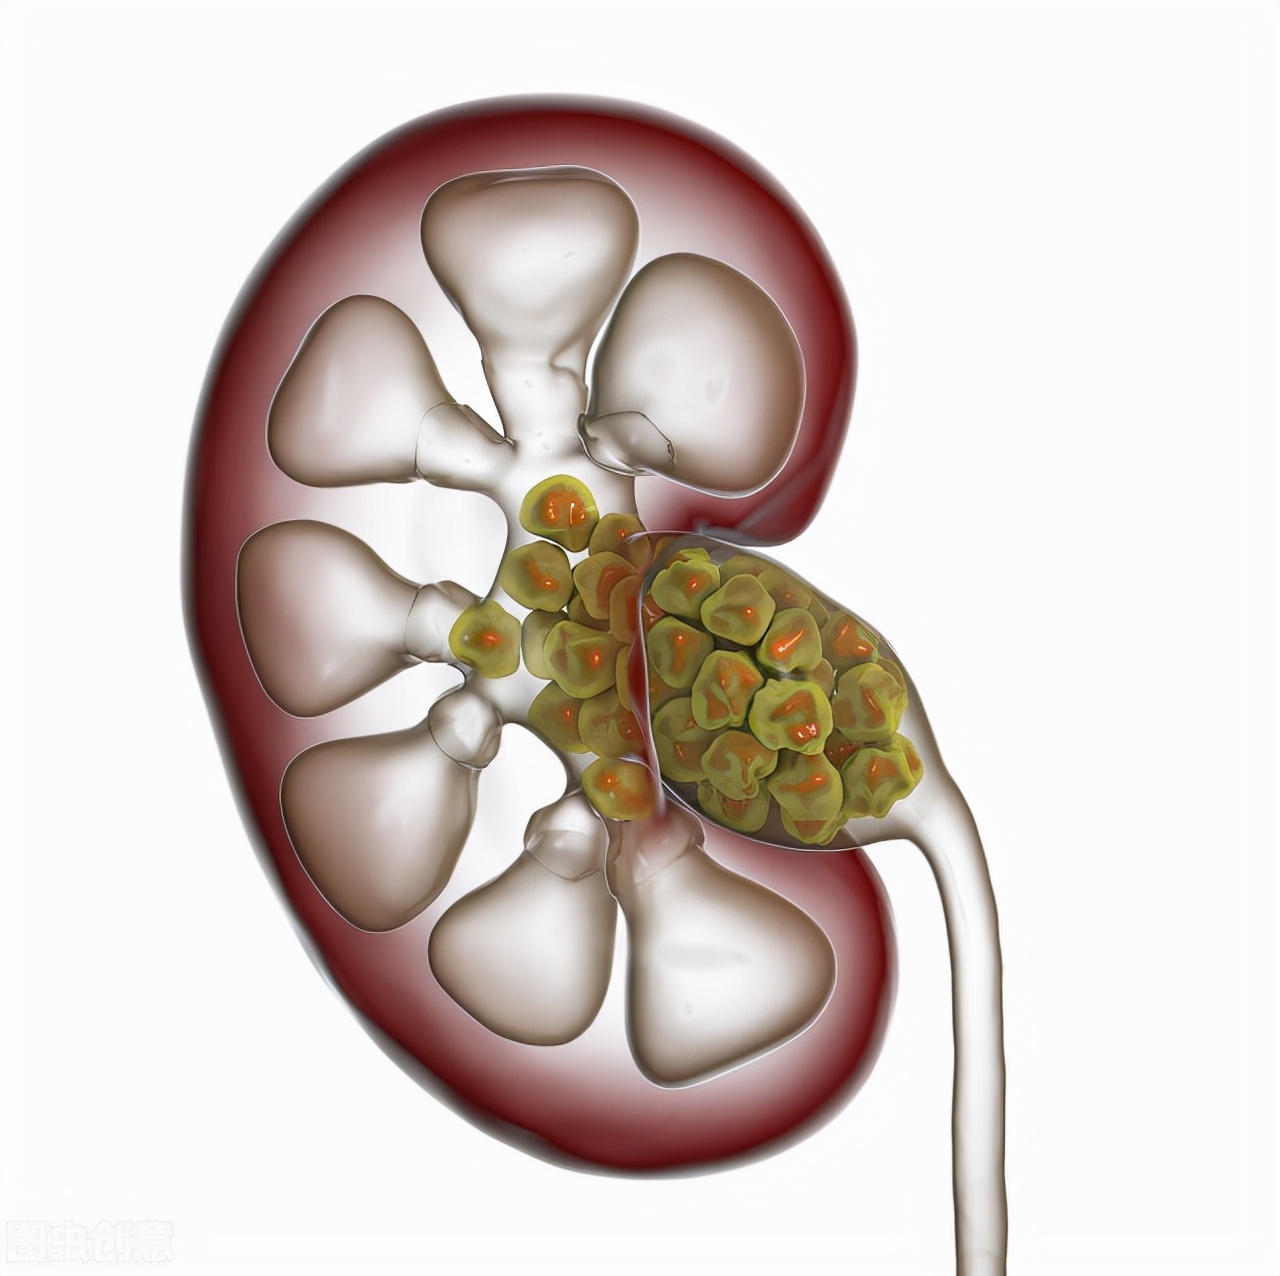

其次,一些内脏器官的疾病也可引起腰酸、腰痛。靠近腰背部的内脏器官发生了病变(如炎症)会引起腰部疼痛,例如:如呼吸系统疾病,胸膜炎、肺结核、支气管肺癌等,但是上述疾病,往往有呼吸系统的症状,比如咳嗽、呼吸困难,而脊柱本身没有压痛、活动受限。再比如,如女性盆腔炎症常会有腰酸、腰痛的感觉,男性如果有肾脏病(如尿路结石,肾下垂,肾盂肾炎)也会出现腰酸、腰痛的情况,但是肾脏病引发的终痛多为钝痛、胀痛、疼痛一般不剧烈,活动和体位改变时疼痛多没有变化,多为双侧疼痛。肾梗死时可为单侧。

肾结石